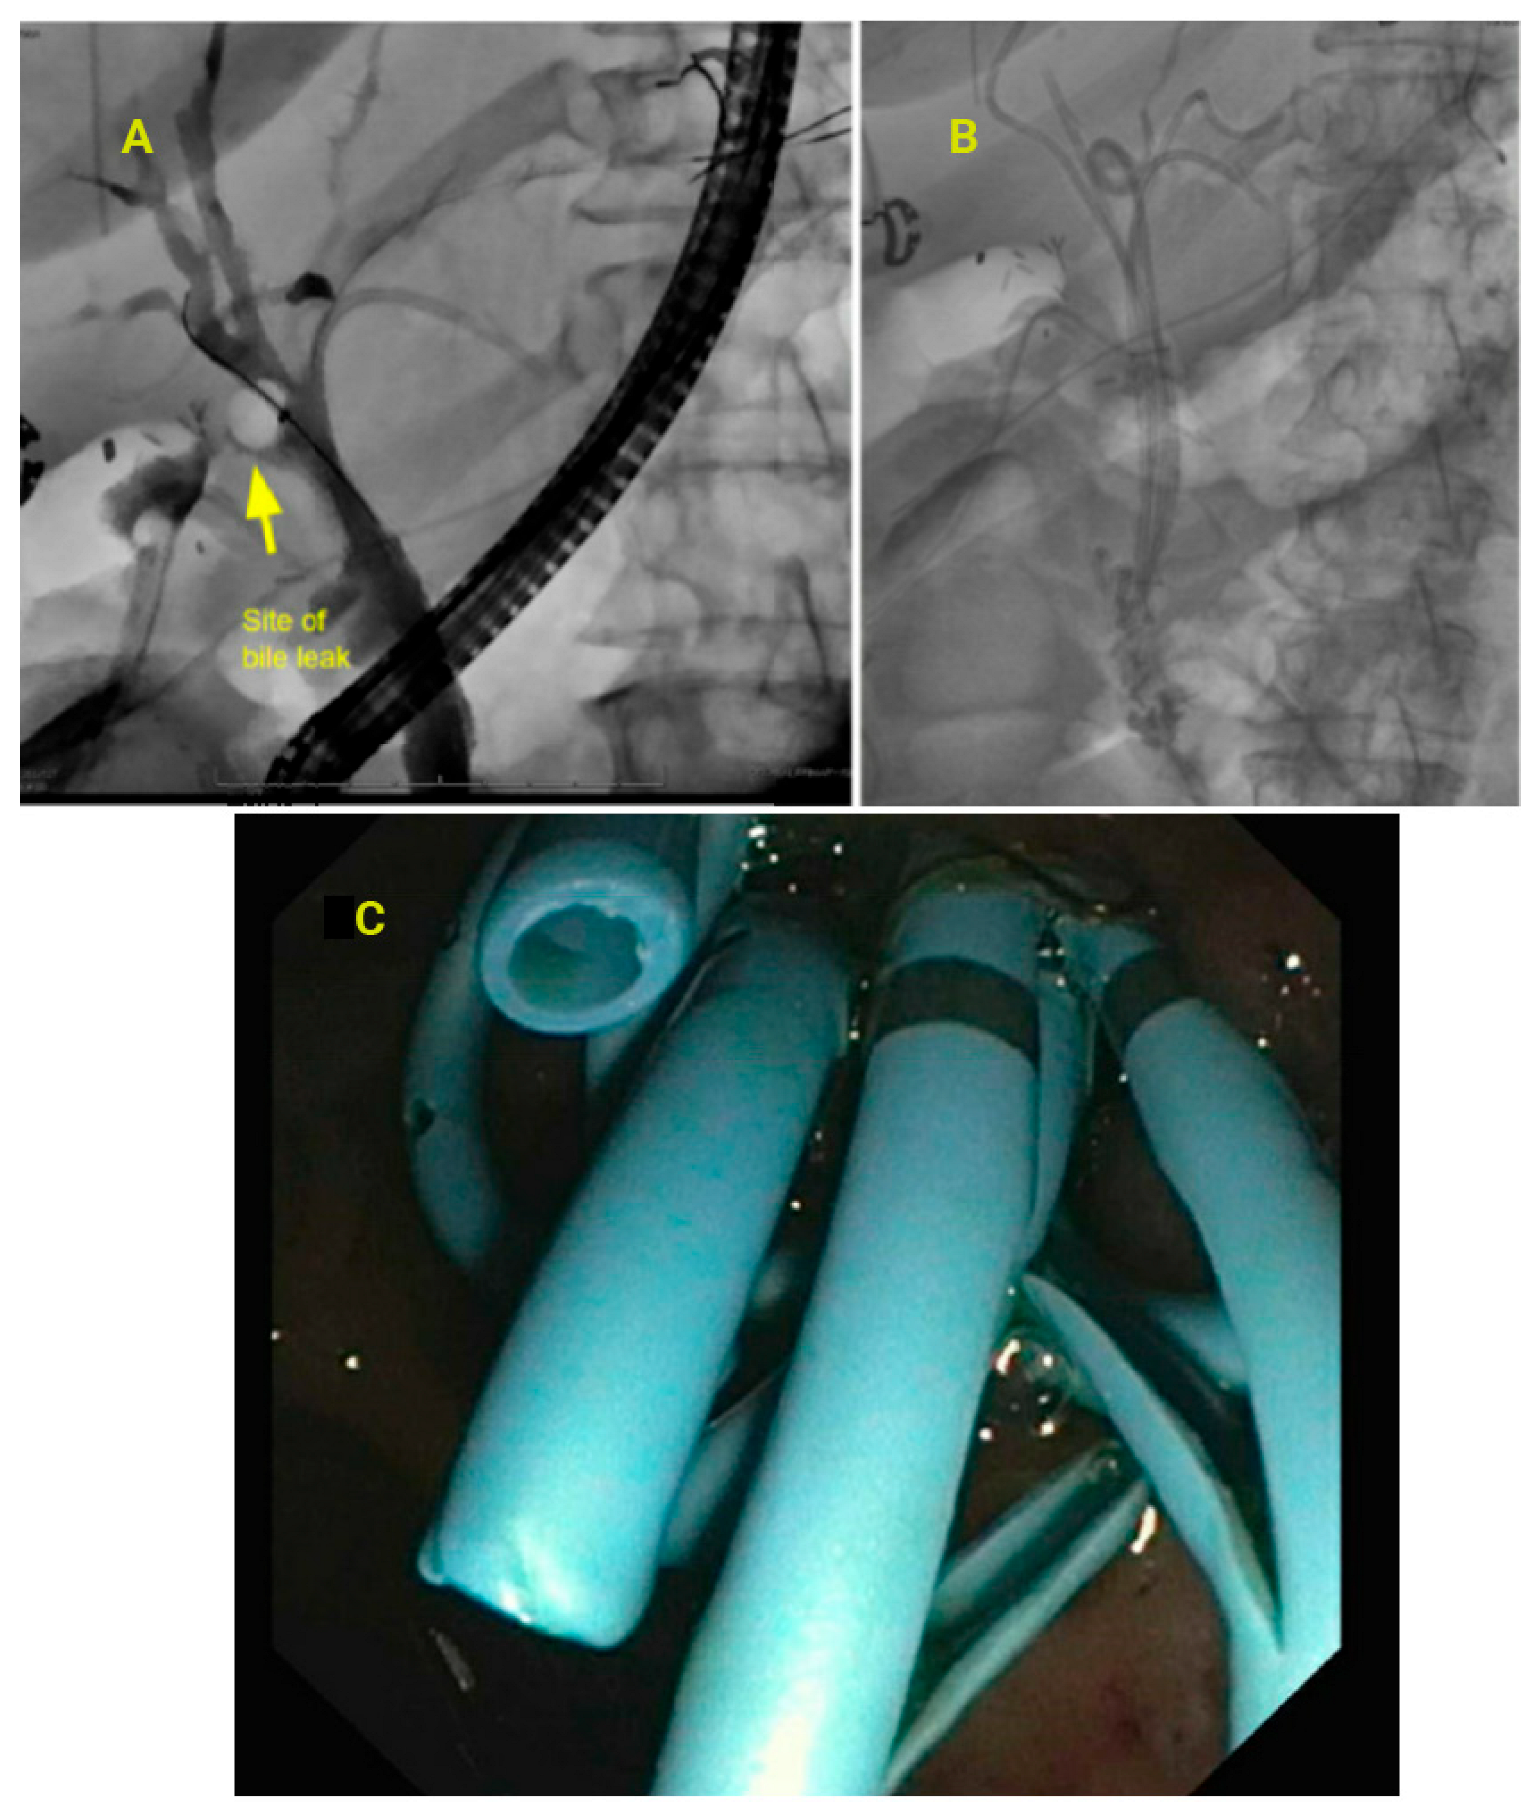

3.9. Bile Leak and Strictures